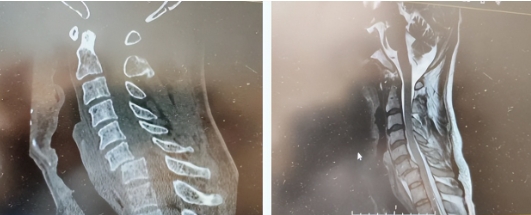

(术前颈6椎体向前Ⅱ°脱位,脊髓明显受压)

(术后,颈6椎体完全复位,前后路内固定位置良好。)